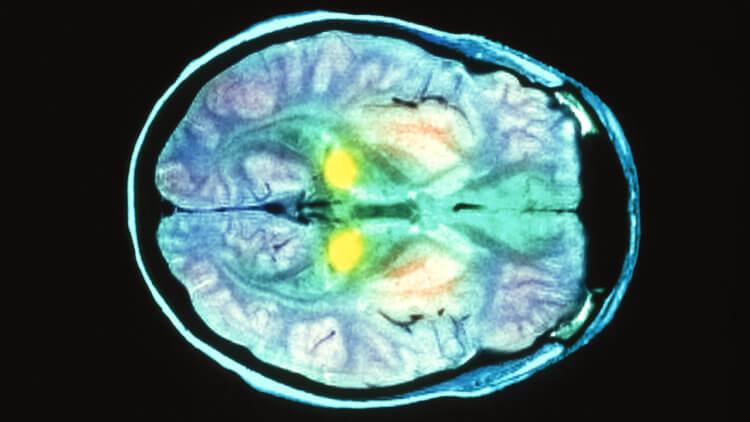

Сканирование мозга пациента с болезнью Крейтцфельдта-Якоба.